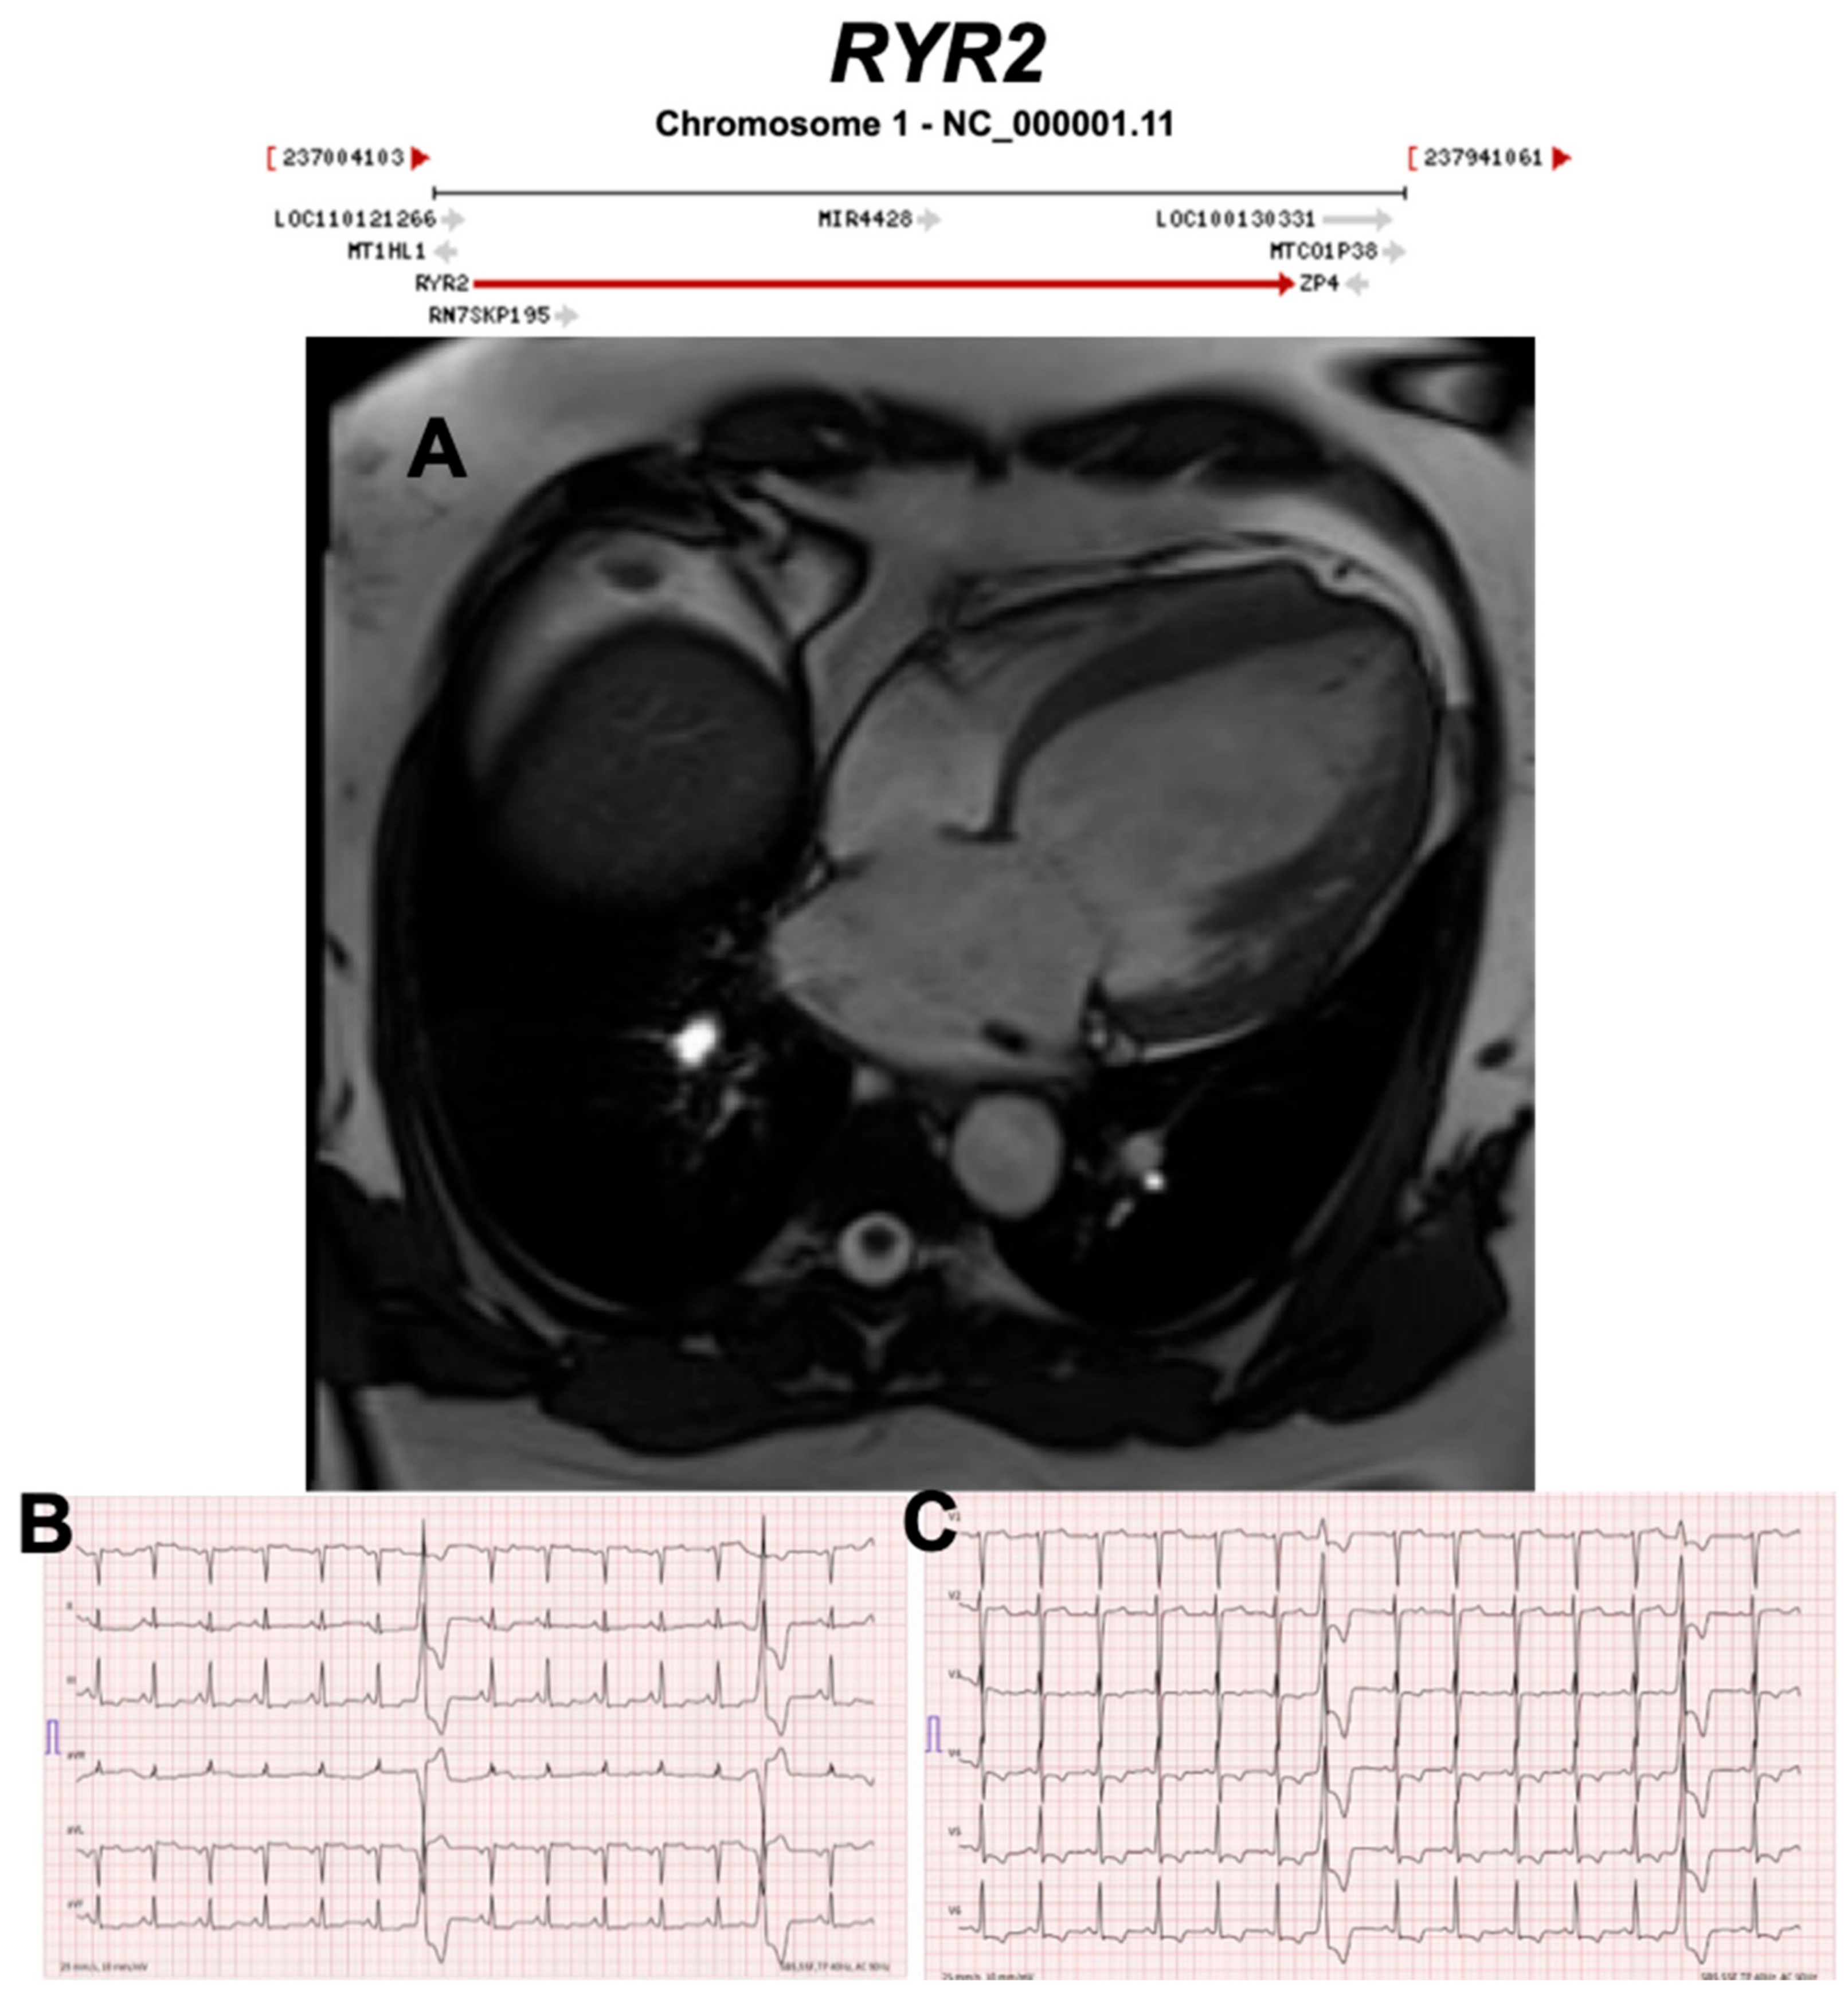

3.2.10. Ryanodine Receptor 2 (RYR2) (Encoded by RYR2)

- Tiso, N.; Stephan, D.A.; Nava, A.; Bagattin, A.; Devaney, J.M.; Stanchi, F.; Larderet, G.; Brahmbhatt, B.; Brown, K.; Bauce, B.; et al. Identification of mutations in the cardiac ryanodine receptor gene in families affected with arrhythmogenic right ventricular cardiomyopathy type 2 (ARVD2). Hum. Mol. Genet. 2001, 10, 189–194. [Google Scholar] [CrossRef] [PubMed]

- Bhuiyan, Z.A.; van den Berg, M.P.; van Tintelen, J.P.; Bink-Boelkens, M.T.; Wiesfeld, A.C.; Alders, M.; Postma, A.V.; van Langen, I.; Mannens, M.M.; Wilde, A.A. Expanding spectrum of human RYR2-related disease: New electrocardiographic, structural, and genetic features. Circulation 2007, 116, 1569–1576. [Google Scholar] [CrossRef] [PubMed]

| RYR2 | Calcium Regulation | 9% | AD | Exon 3 deletion DCM | ARVC2 | 1q43; 107 | CPVT | Refuted for ARVC, Definitive for CPVT |

| Conflicting evidence of misdiagnosis CPVT as ARVC with the exception of exon 3 deletions associated with structural abnormalities. | ||||||||